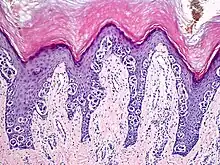

An acral nevus is a cutaneous condition of the palms, soles, fingers, or toes (peripheral body parts), characterized by a skin lesion that is usually macular or only slightly elevated, and may display a uniform brown or dark brown color, often with linear striations.[1]: 1726

Acral nevi may occur in all ethnic groups, but are more common in dark-skinned people. The acral nevus is a benign skin lesion that can occur at any age, but is generally noticed between 10 and 30 years of age. Both children and adults may be observed with this skin lesion. The prevalence of acral nevi increases directly with degree of skin pigmentation. In a study, palmar or plantar nevi were detected in 42.0% of black (50 of 119) vs 23.0% of whites (79 of 343). Palmar or plantar nevi of 6 mm diameter or larger were detected in 3.4% of blacks (4 of 119) vs 0.6% of whites.[2]

They are brown to dark brown in color and have linear streaks of darker pigmentation. Size is usually 7 mm or less, oval or spindle shaped, and well-demarcated. They become stable after an initial growth phase, and the number of lesions also decreases; a new lesion in middle-aged or elderly people should raise suspicion of acral lentiginous melanoma.